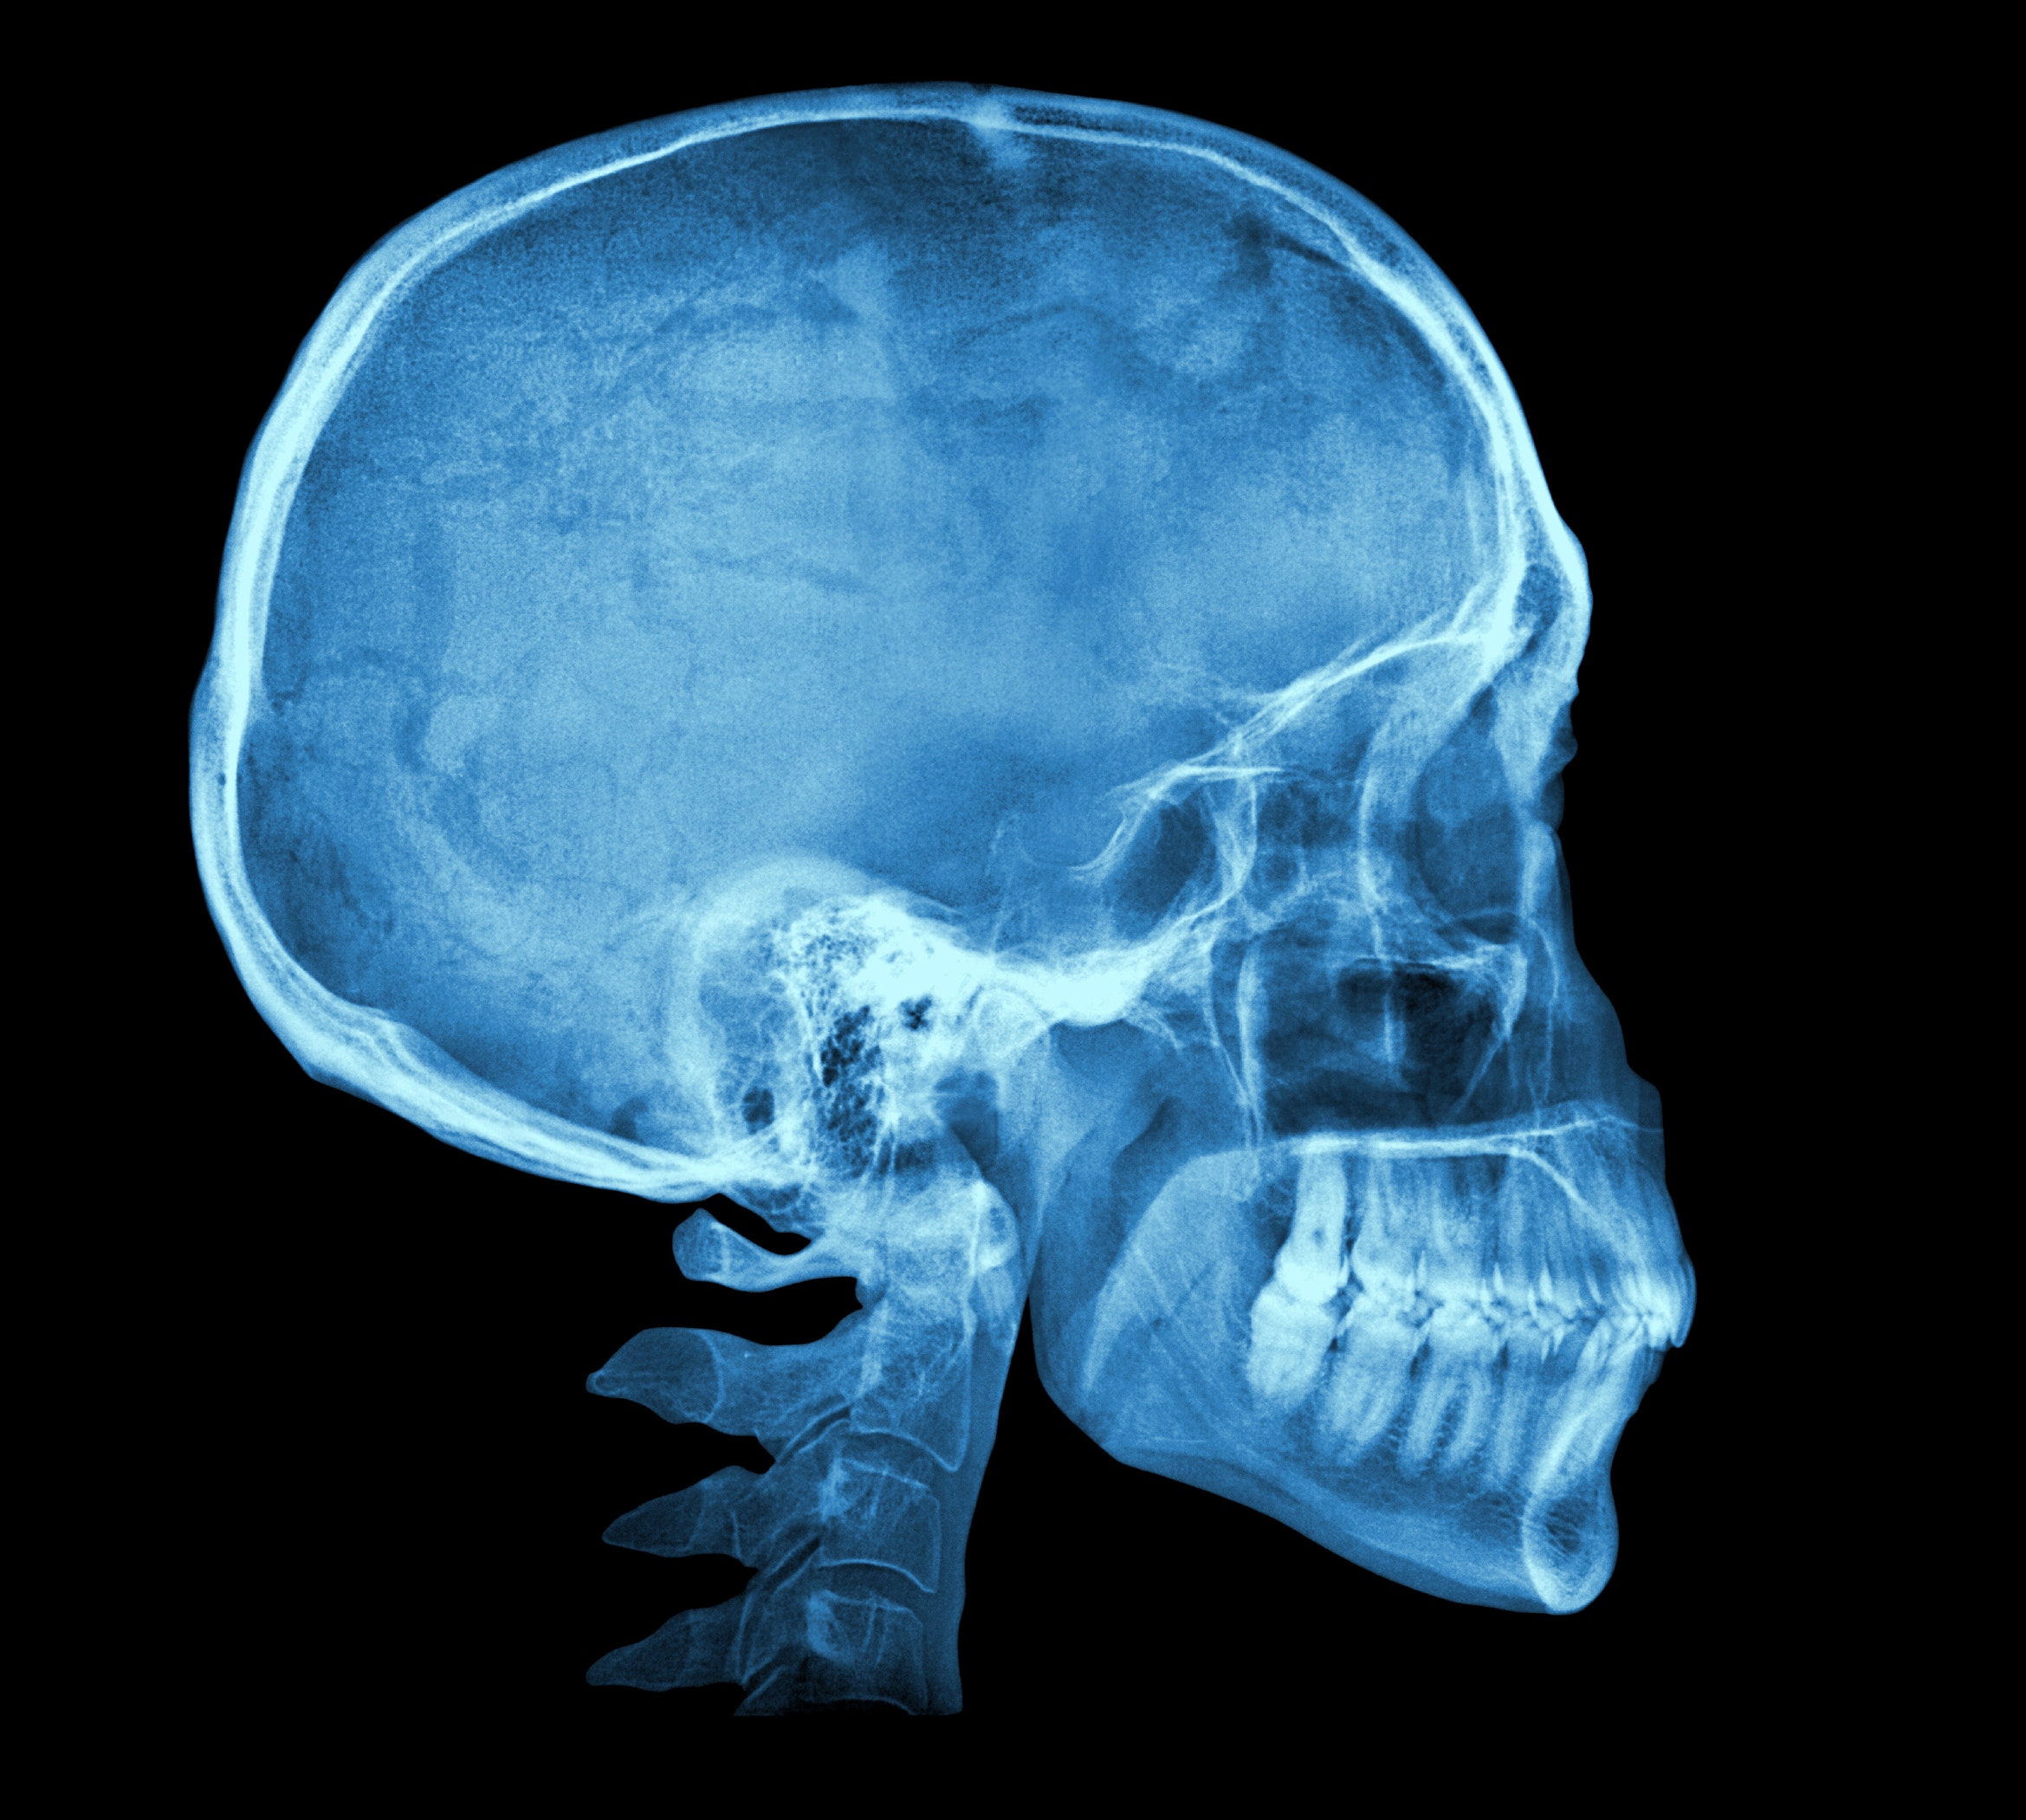

Рентгенография черепа и позвоночника: изображение и диагностика